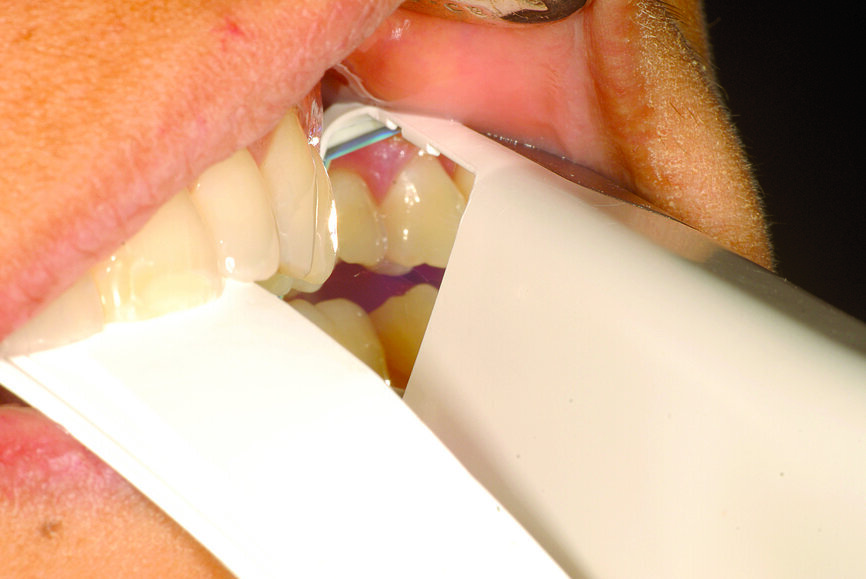

Fig. 22: Analogue recording of centric relation using a composite device to stabilise the mandible and polyvinylsiloxane recording paste.

Fig. 23: Analogue recording of centric relation using a composite device to stabilise the mandible and polyvinylsiloxane recording paste.

Fig. 24: Centric relation recording using an intra-oral scanner while the mandible is stabilised by a leaf gauge at the desired vertical dimension of occlusion.

The technique for recording the CR position can be performed using analogue (Figs. 22 & 23) or digital methods (Figs. 24–27).